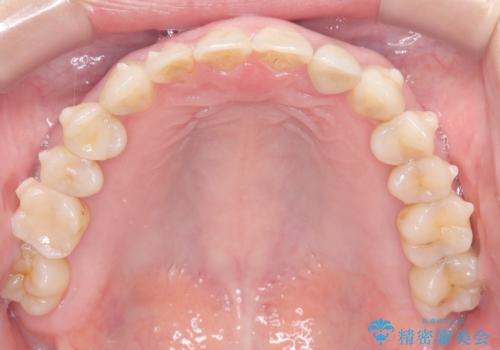

精密検査の結果、全体の隙間を閉じるだけでは適切な咬合バランスが得られないため、まずはインビザラインを用いて歯の位置を理想的な場所へと整える計画を立案しました。矯正によって欠損部位に適切なスペースを確保した後、その部分にインプラントを埋入することで、審美性と機能性の両立を目指しました。

治療は、まずインビザラインを使用して全体の隙間を閉じつつ、将来インプラントを入れるためのスペースをミリ単位で精密に調整しました。マウスピース矯正は、歯の移動量をデジタルで管理できるため、最終的な被せ物の大きさに合わせた理想的な位置取りが可能です。